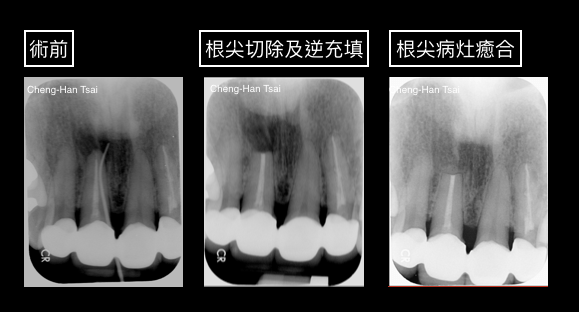

顯微根尖手術可以藉著顯微鏡底下的視野,精細地將傳統根管治療無法解決的根尖切除,並用特殊材料做根尖的逆充填處理,以期達到消除感染、保留牙齒的目的。

醫師會先經過影像學的評估後(通常需要牙科電腦斷層),在局部麻醉下把牙肉翻開,並暴露出根尖感染的部位。在顯微鏡下把牙根外發炎感染的肉芽組織刮除清理,並染色確認牙根有無裂痕(若高度懷疑裂齒),最後將感染嚴重的根尖切除,並使用特殊的生物相容性高之封填材將根尖孔做逆向充填,再依需要放置骨粉、再生膜等牙周再生材料,最後將皮瓣復位。

術前:牙套密合度尚可,病人不想拆除長距離牙橋,且根尖感染嚴重經專科醫師評估後進行根尖手術。

術後:拆線癒合後只有一非常不明顯白色疤痕,術前的牙根尖軟組織腫脹已完全消失。X光也顯示根尖破壞的完全癒合。